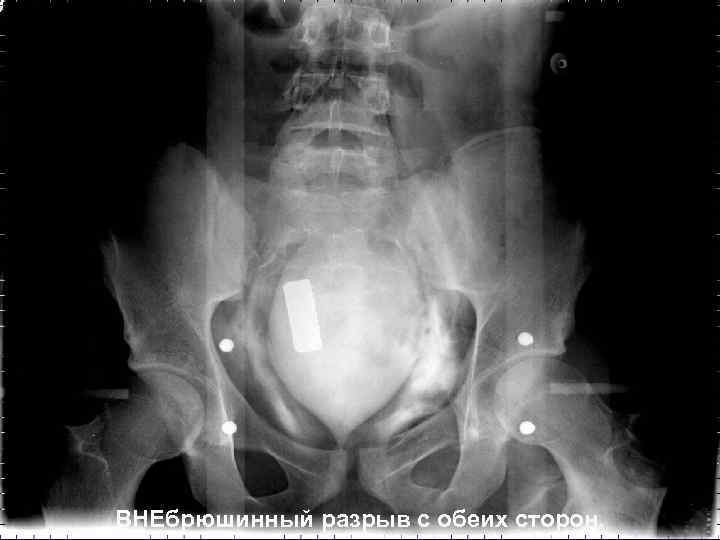

ЦИСТОГРАФИЯ q. Обзорная урография; q. Ретроградная уретрография (при подозрении на травму уретры); q. МП заполняется контрастом через катетер, на 350 -400 мл. → снимки в прямой и боковой проекции; q. Снимок после опорожнения МП.

ВНЕбрюшинный разрыв с обеих сторон.